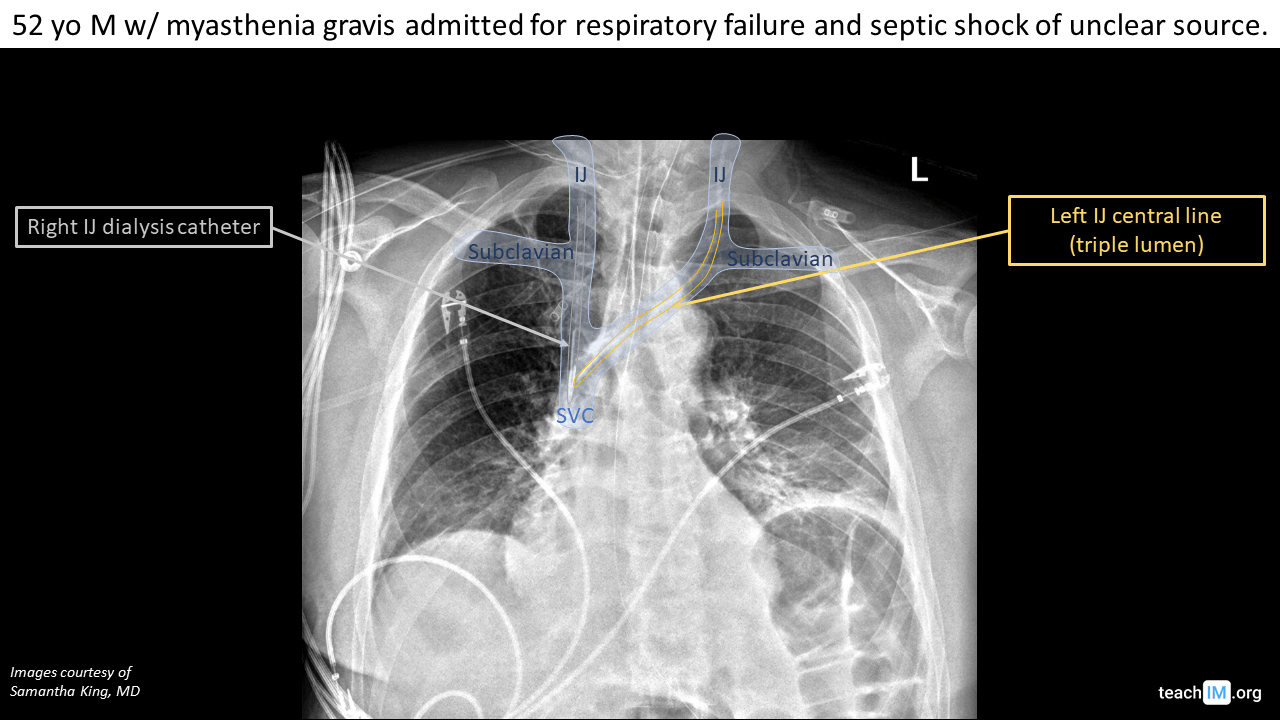

Complicaciones de un catéter venoso central

• Neumotórax

• Taponamiento cardíaco por lesión miocárdica

• Punción arterial

Realizar CXR portátil posterior a su colocación y previo a la administración de medicamentos: punta del catéter debe estar proximal al ángulo entre la tráquea y el bronquio principal derecho